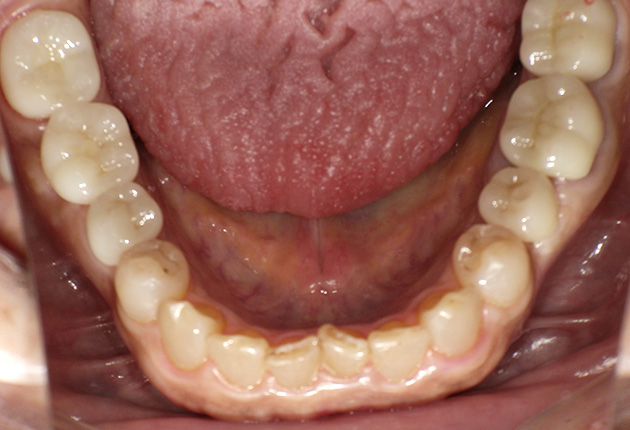

よく噛めず笑うと銀歯が目立つので気にされていました。

| 主訴 | ブリッジ脱離、しっかり噛めない |

| 診査診断 | 上顎歯牙欠損、歯周病、不良補綴、根尖性周囲炎。 不正咬合により噛み合わせのバランスが悪い事が原因により咬合治療が必要。 |

| 治療内容 | 欠損部インプラント 不正咬合に対し不良補綴のやり直しと合わせて咬合再構築 |